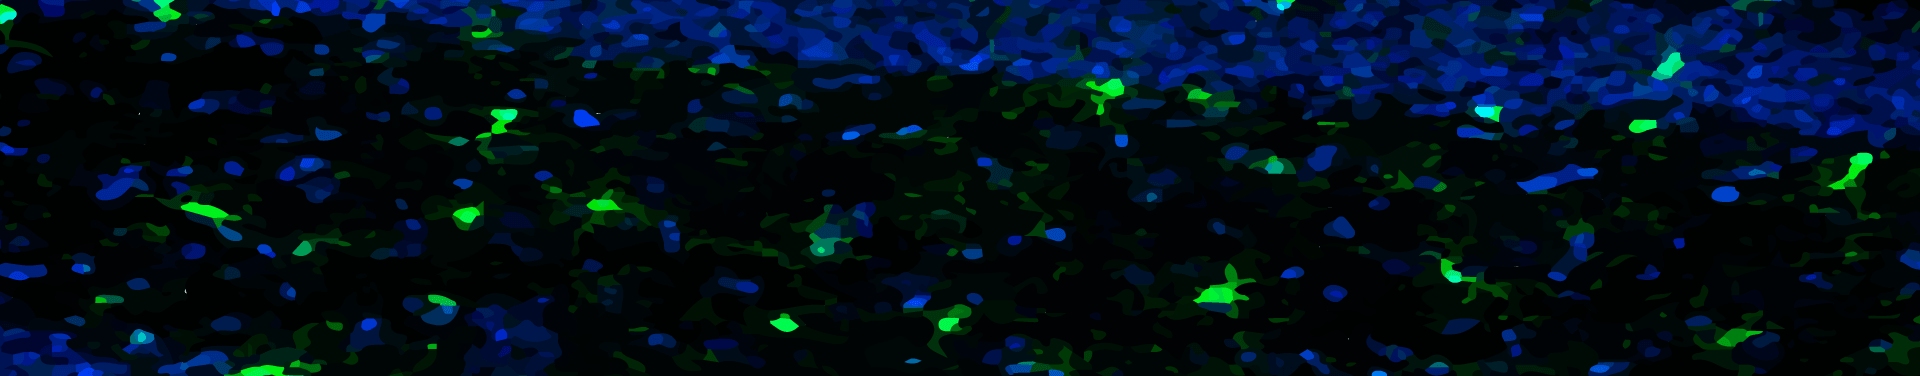

Our research shows that overfeeding in early life can contribute to central inflammation that may permanently influence hypothalamic feeding and stress circuitry; leading to an increased propensity to gain weight and stay fat, hyperactive responses to stress, infertility, and an inability to appropriately respond to inflammatory challenges.

We have a particular focus on the role of microglia in these effects and are also establishing microglia’s role in healthy brain function, including appetite and cognition.